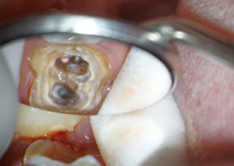

重度の虫歯には根管治療

虫歯菌が神経にまで到達すると、神経を取る必要があります。

根管治療とは、歯根にある根管から虫歯になってしまった神経や血管を除去し、洗浄、殺菌をした後、薬剤を詰めて被せ物をする方法です。高度な技術を要しますが、根管治療によって自分の歯を長く維持できるようになります。

当院でのマイクロスコープを用いたより精度の高い根管治療

お口の中は暗く狭いため、肉眼では細部まで見ることができません。

当院では、肉眼の20倍まで拡大できる歯科用マイクロスコープを用いて診療を行っております。マイクロスコープを用いることで、通常よりも、より確実で精度の高い治療を行うことができます。

尚、当院では、マイクロスコープを用いた根管治療を健康保険内で行っております。